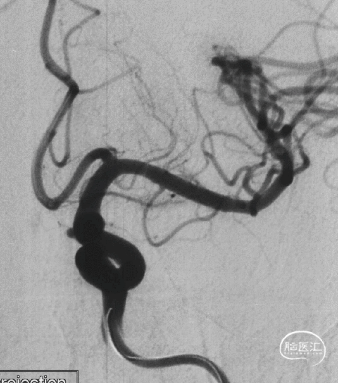

现病史:患者因头痛17天,外院行头颅CTA提示:左侧颈内动脉交通段动脉瘤,动脉瘤大小约5.3×5.4mm,形态不规则,左侧大脑前动脉A1段瘤样凸起。

可见一小泡自动脉瘤瘤体上发出

瘤体最大径6.92mm

远端血管直径:3.28mm

近端血管直径:3.98mm

同侧A1可见一小瘤突起